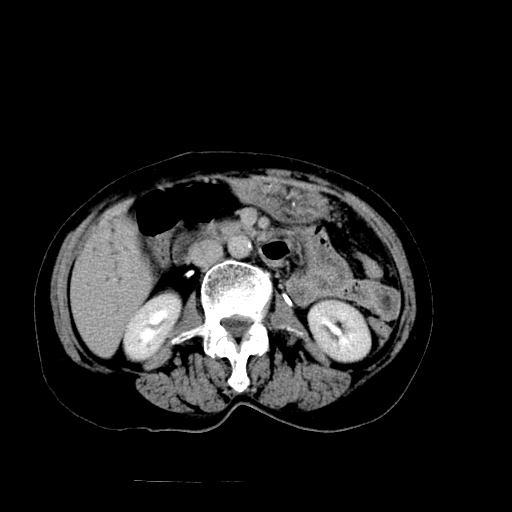

以下是引用随光逐影在2009-4-7 8:21:00的发言:[br]肝内外胆管多发性结石并肝内外胆管扩张;胆系感染。